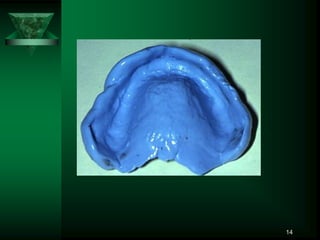

14